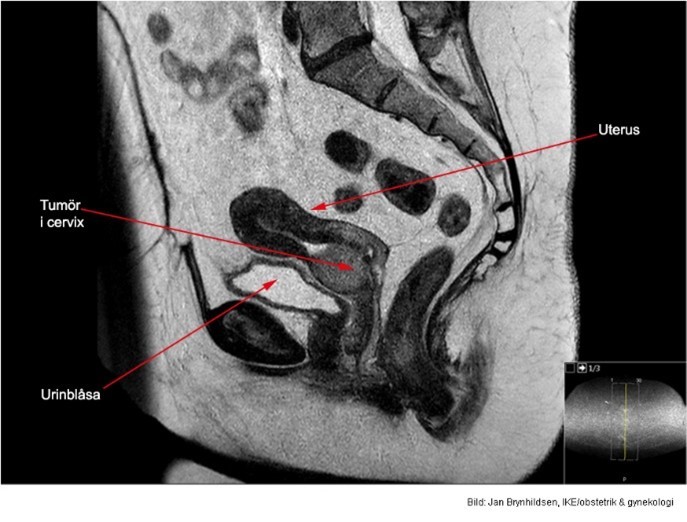

Vad visar bilden?

3x4 cm stor cervixtumör utan hållpunkter för spridning.